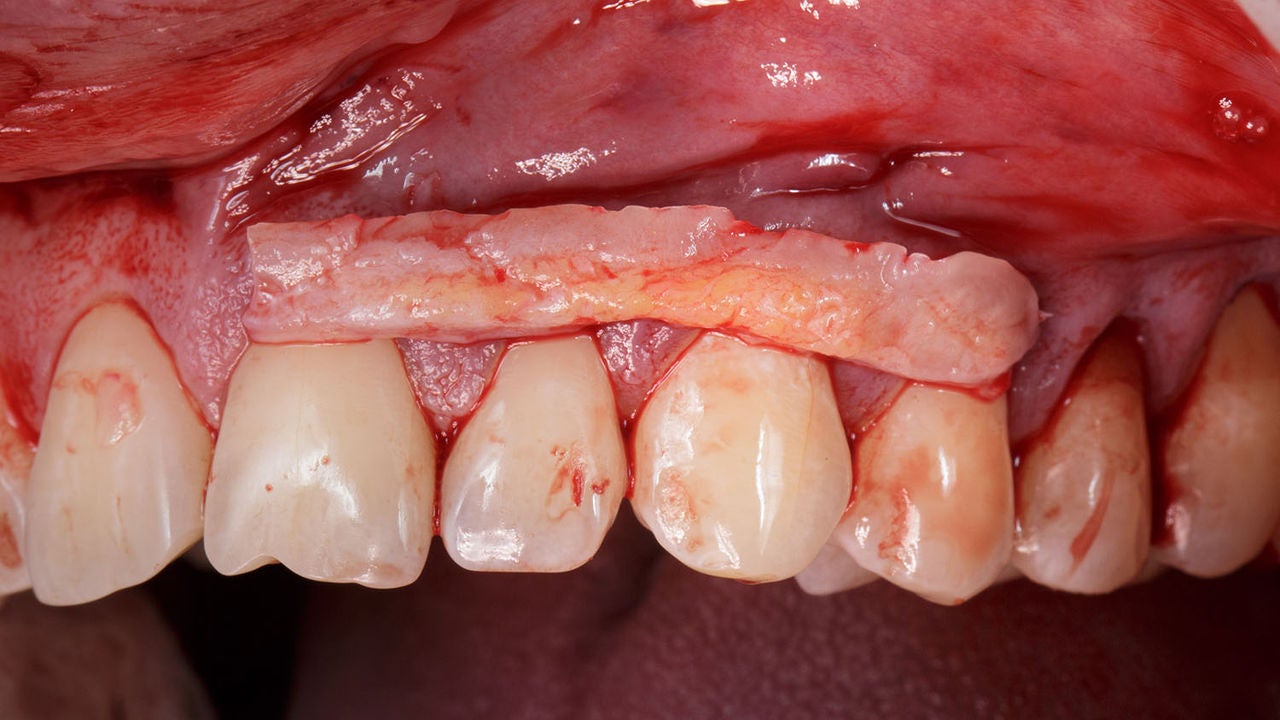

Damaktan et alıp diş eti yapmak için doktor ağzın çatı kısmını oluşturan sağlıklı damak dokusundan gereken miktar kadar et alır ve diş etlerinin çekildiği bölgeye taşır. (1) Diş eti grefti işlemi aşamaları aşağıdakileri kapsayabilir:

- Diş eti grefti için doku alınacak bölgedeki diş ve ediş etleri lokal anestezi ile uyuşturulur. Uyuşma sonrası diş etlerine kesi uygular ve bu arada diş köklerini de temizler. Ardından damak bölgesinde kesi yapar ve küçük bir doku parçası çıkarır. (1)

- Çıkarılan doku parçası, damaktan et alıp diş eti yapmak için diş eti çekilmesinin yaşandığı bölgelere yerleştirilir. Diş eti dokusunu uygun bir şekilde konumlandırarak sabit kalması için dikiş uygular. Genellikle kendiliğinden düşen dikişler kullanılır. Hangi dikiş işlemin uygulanacağı doktor tarafından belirlenir. (1)